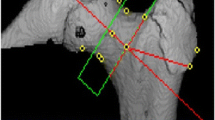

Bone densitometry, anthropometric parameters, and hip structural analysis

The femur neck was scanned at the left hip in the posteroanterior projection using dual X-ray absorptiometry (DXA) (QDR4500A; Hologic, Bedford, MA, USA) equipment located in mobile examination centers according to manufacturer protocol. All scans were further analyzed for geometric bone structure properties using the hip structure analysis (HSA) program included in APEX software of Hologic, as previously described [11, 12]. The HSA program automatically set the region of interest (ROI), defined as the narrow neck (NN), transversing the narrowest width of the femoral neck. In addition to hip axis length (HAL, mm), femur neck width (FNW, cm), and neck shaft angle (NSA, degree), the HSA program yielded data for cross-sectional area (CSA, cm2), cross-sectional moment of inertia (CSMI, cm4), mean cortical thickness (CT, cm), section modulus (SM, cm3), and buckling ratio (BR) at NN. Short-term coefficient of variance (CV) of HSA indices, calculated from the same images used for the precision assessment of BMD, appeared to be slightly greater than those of conventional BMD, but were approximately 2 %, which seemed to be similar to previously reported precision data [13, 14]. Whole-body DXA was also acquired and analyzed using Hologic Discovery software version 12.1 in its default configuration. DXA calibrations were applied as previously described [15].